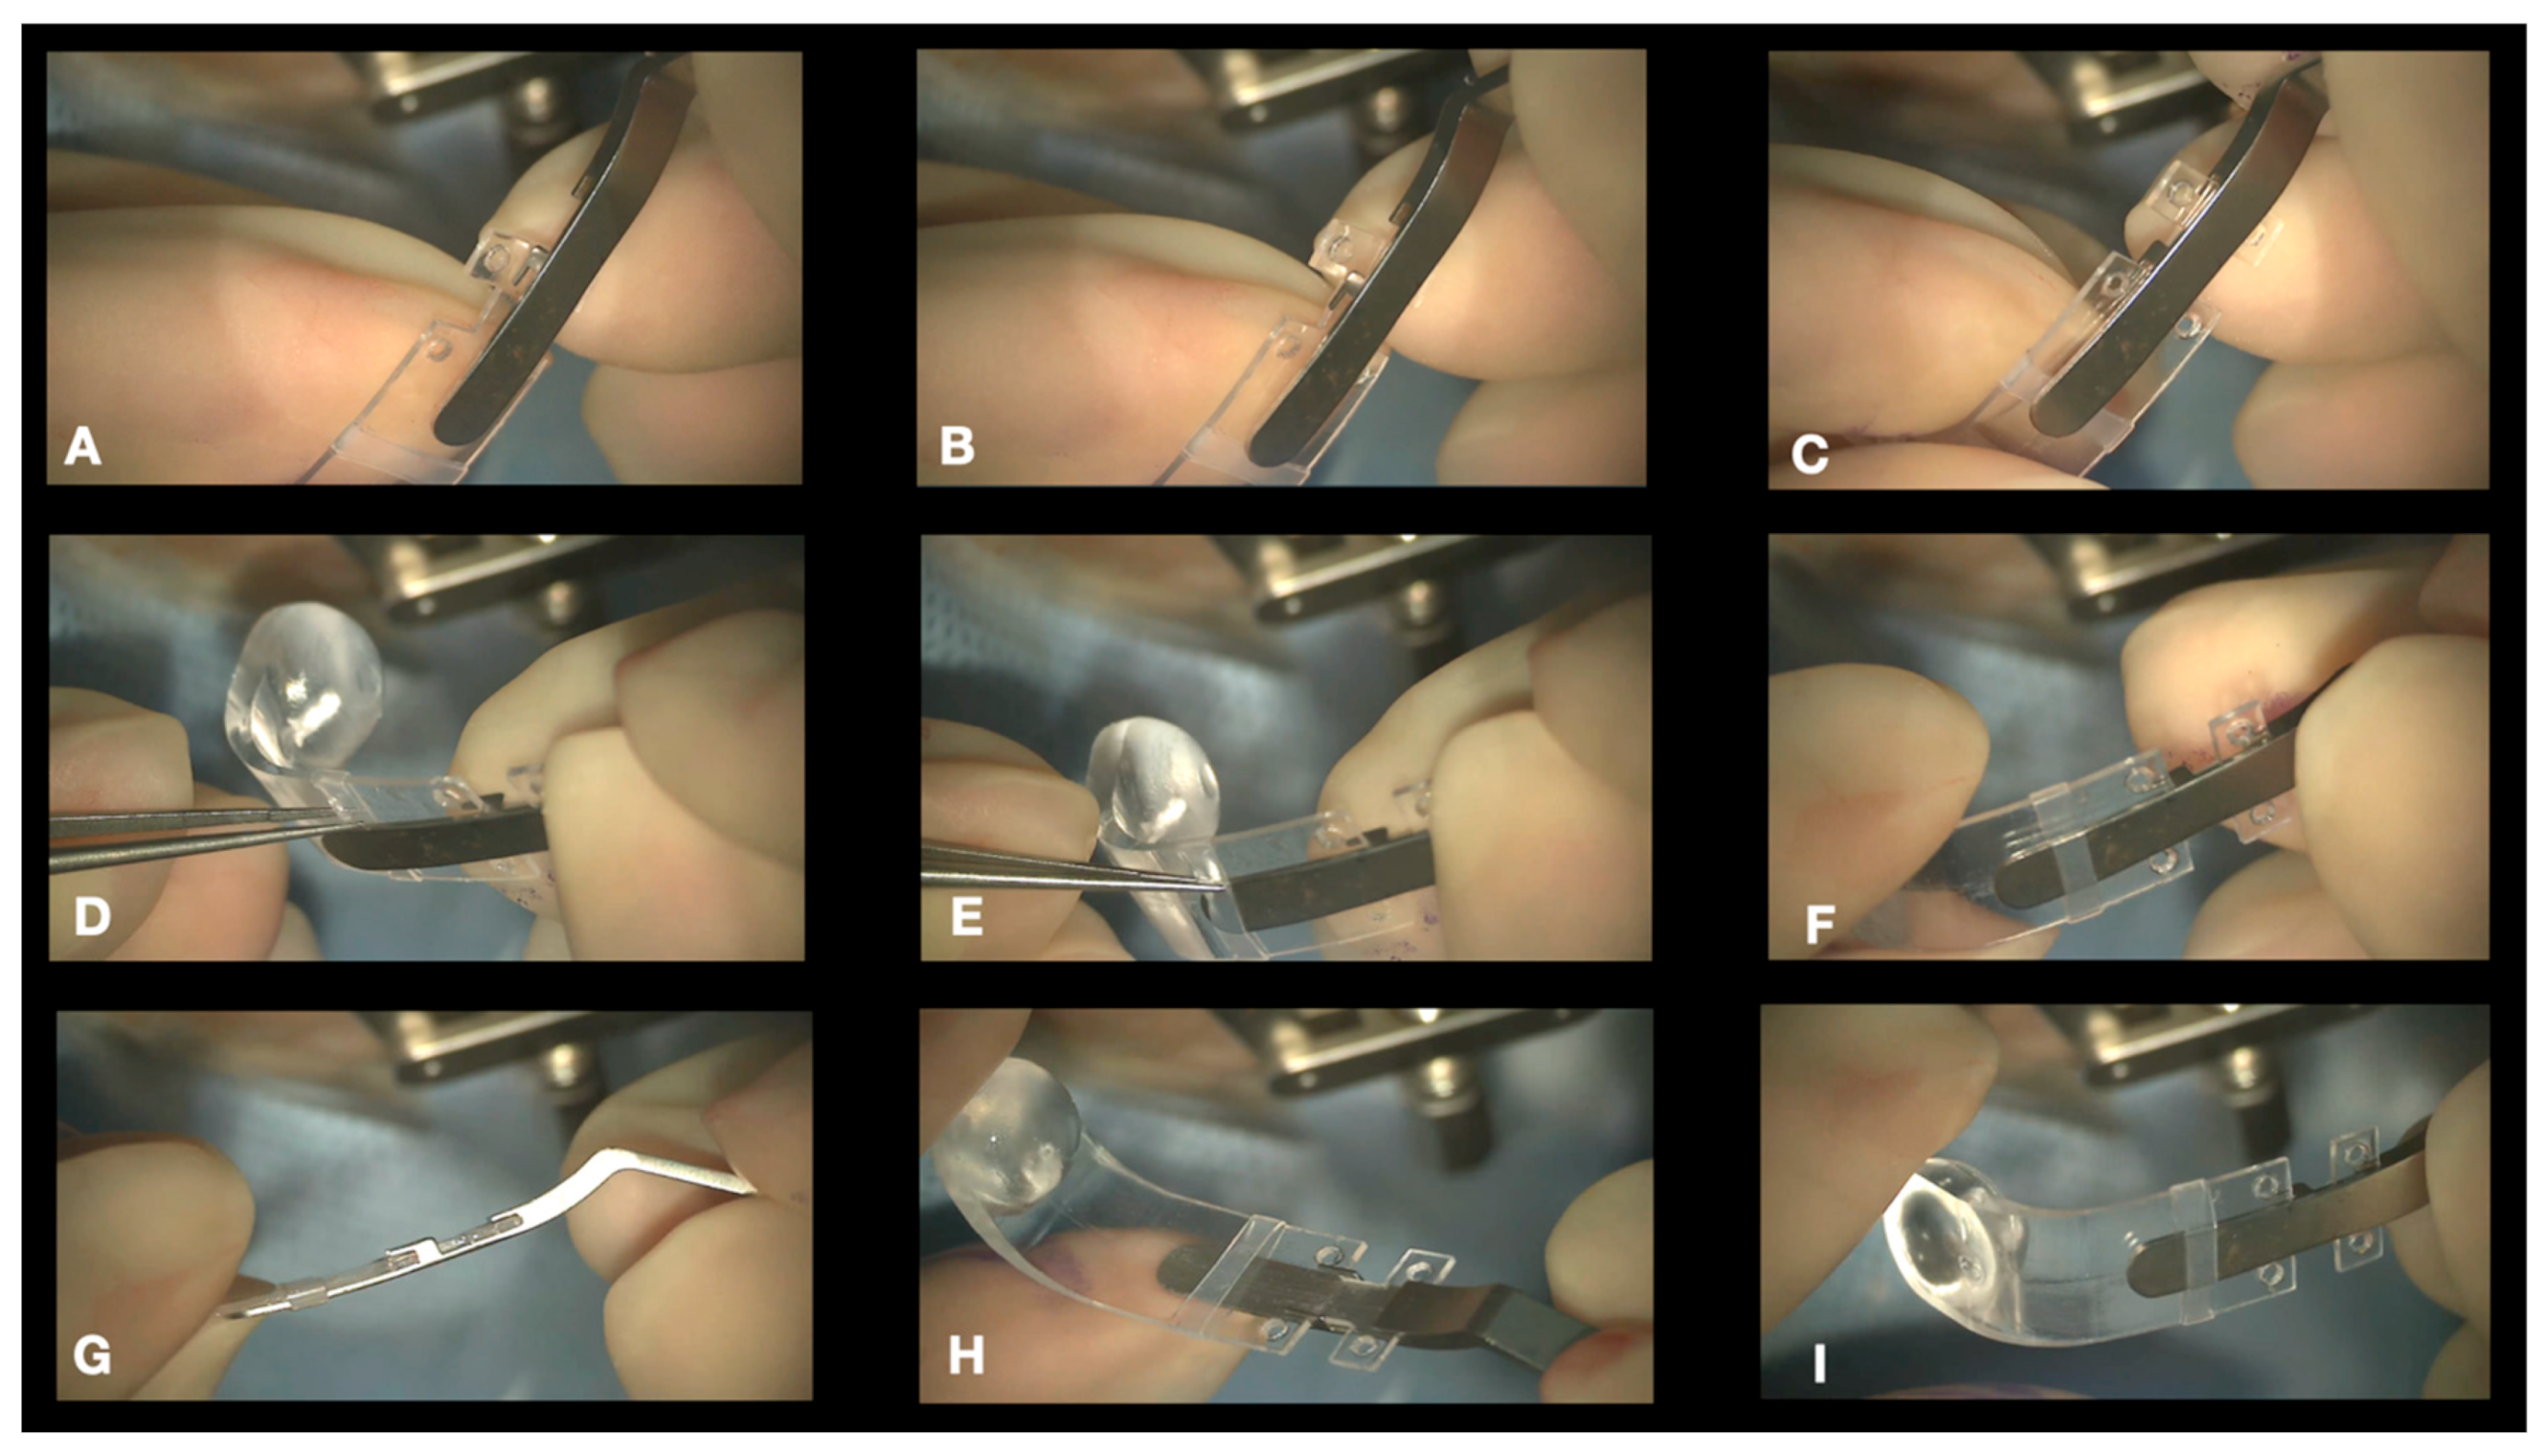

- Connecting the NPB on the NPD Loading device. We suggest connecting the NPB to the NPB loading device (Figure 6). As an alternative, the NPB can be held with bayoneted forceps, but attention should be taken not to break the NPB. To connect the NPB to the NPB loading device, it is necessary to execute the following steps:

- Hold the handle of the NPB loading device.

- Align the tip of the loading device to the external side of the NPB arm.

- Insert the tip of the loading device into the silicone sleeve with the help of non-toothed forceps.

- Connect the teeth of the loading device, embracing the NPB anterior wings.

- Position Check. The position of the NPB is checked through the microscope by moving the NPB with the NPB loading device or with strong forceps (Figure 10a,b). If the location is correct, the surgeon can go to step 8; otherwise, the sutures should be adjusted until the buckle is well centered.

- 8.

- Disconnecting the NPB Loading Device From the NPB. If the NPB loading device was used, at the end of the procedure, it must be carefully disconnected from the NPB. We advise to keep the NPB’s most anterior wing steady with non-toothed forceps and to gently elevate it by 1mm and pull the NPB loading device out.